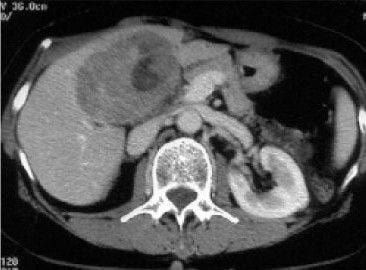

Fig. TC de la parte superior del abdomen de un paciente con carcinoma del intestino grueso que muestra metástasis múltiple hacia el hígado.